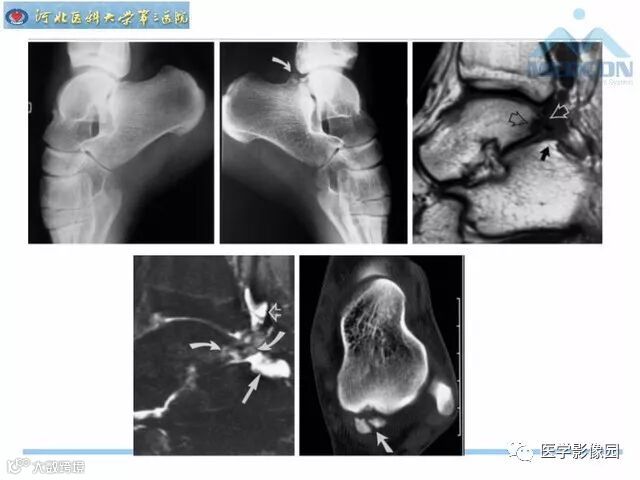

踝关节撞击综合征影像诊断,干货满满,值得收藏!

导读:踝关节撞击综合征影像诊断。干货满满,值得收藏!

踝关节撞击综合征影像诊断。干货满满,值得收藏!